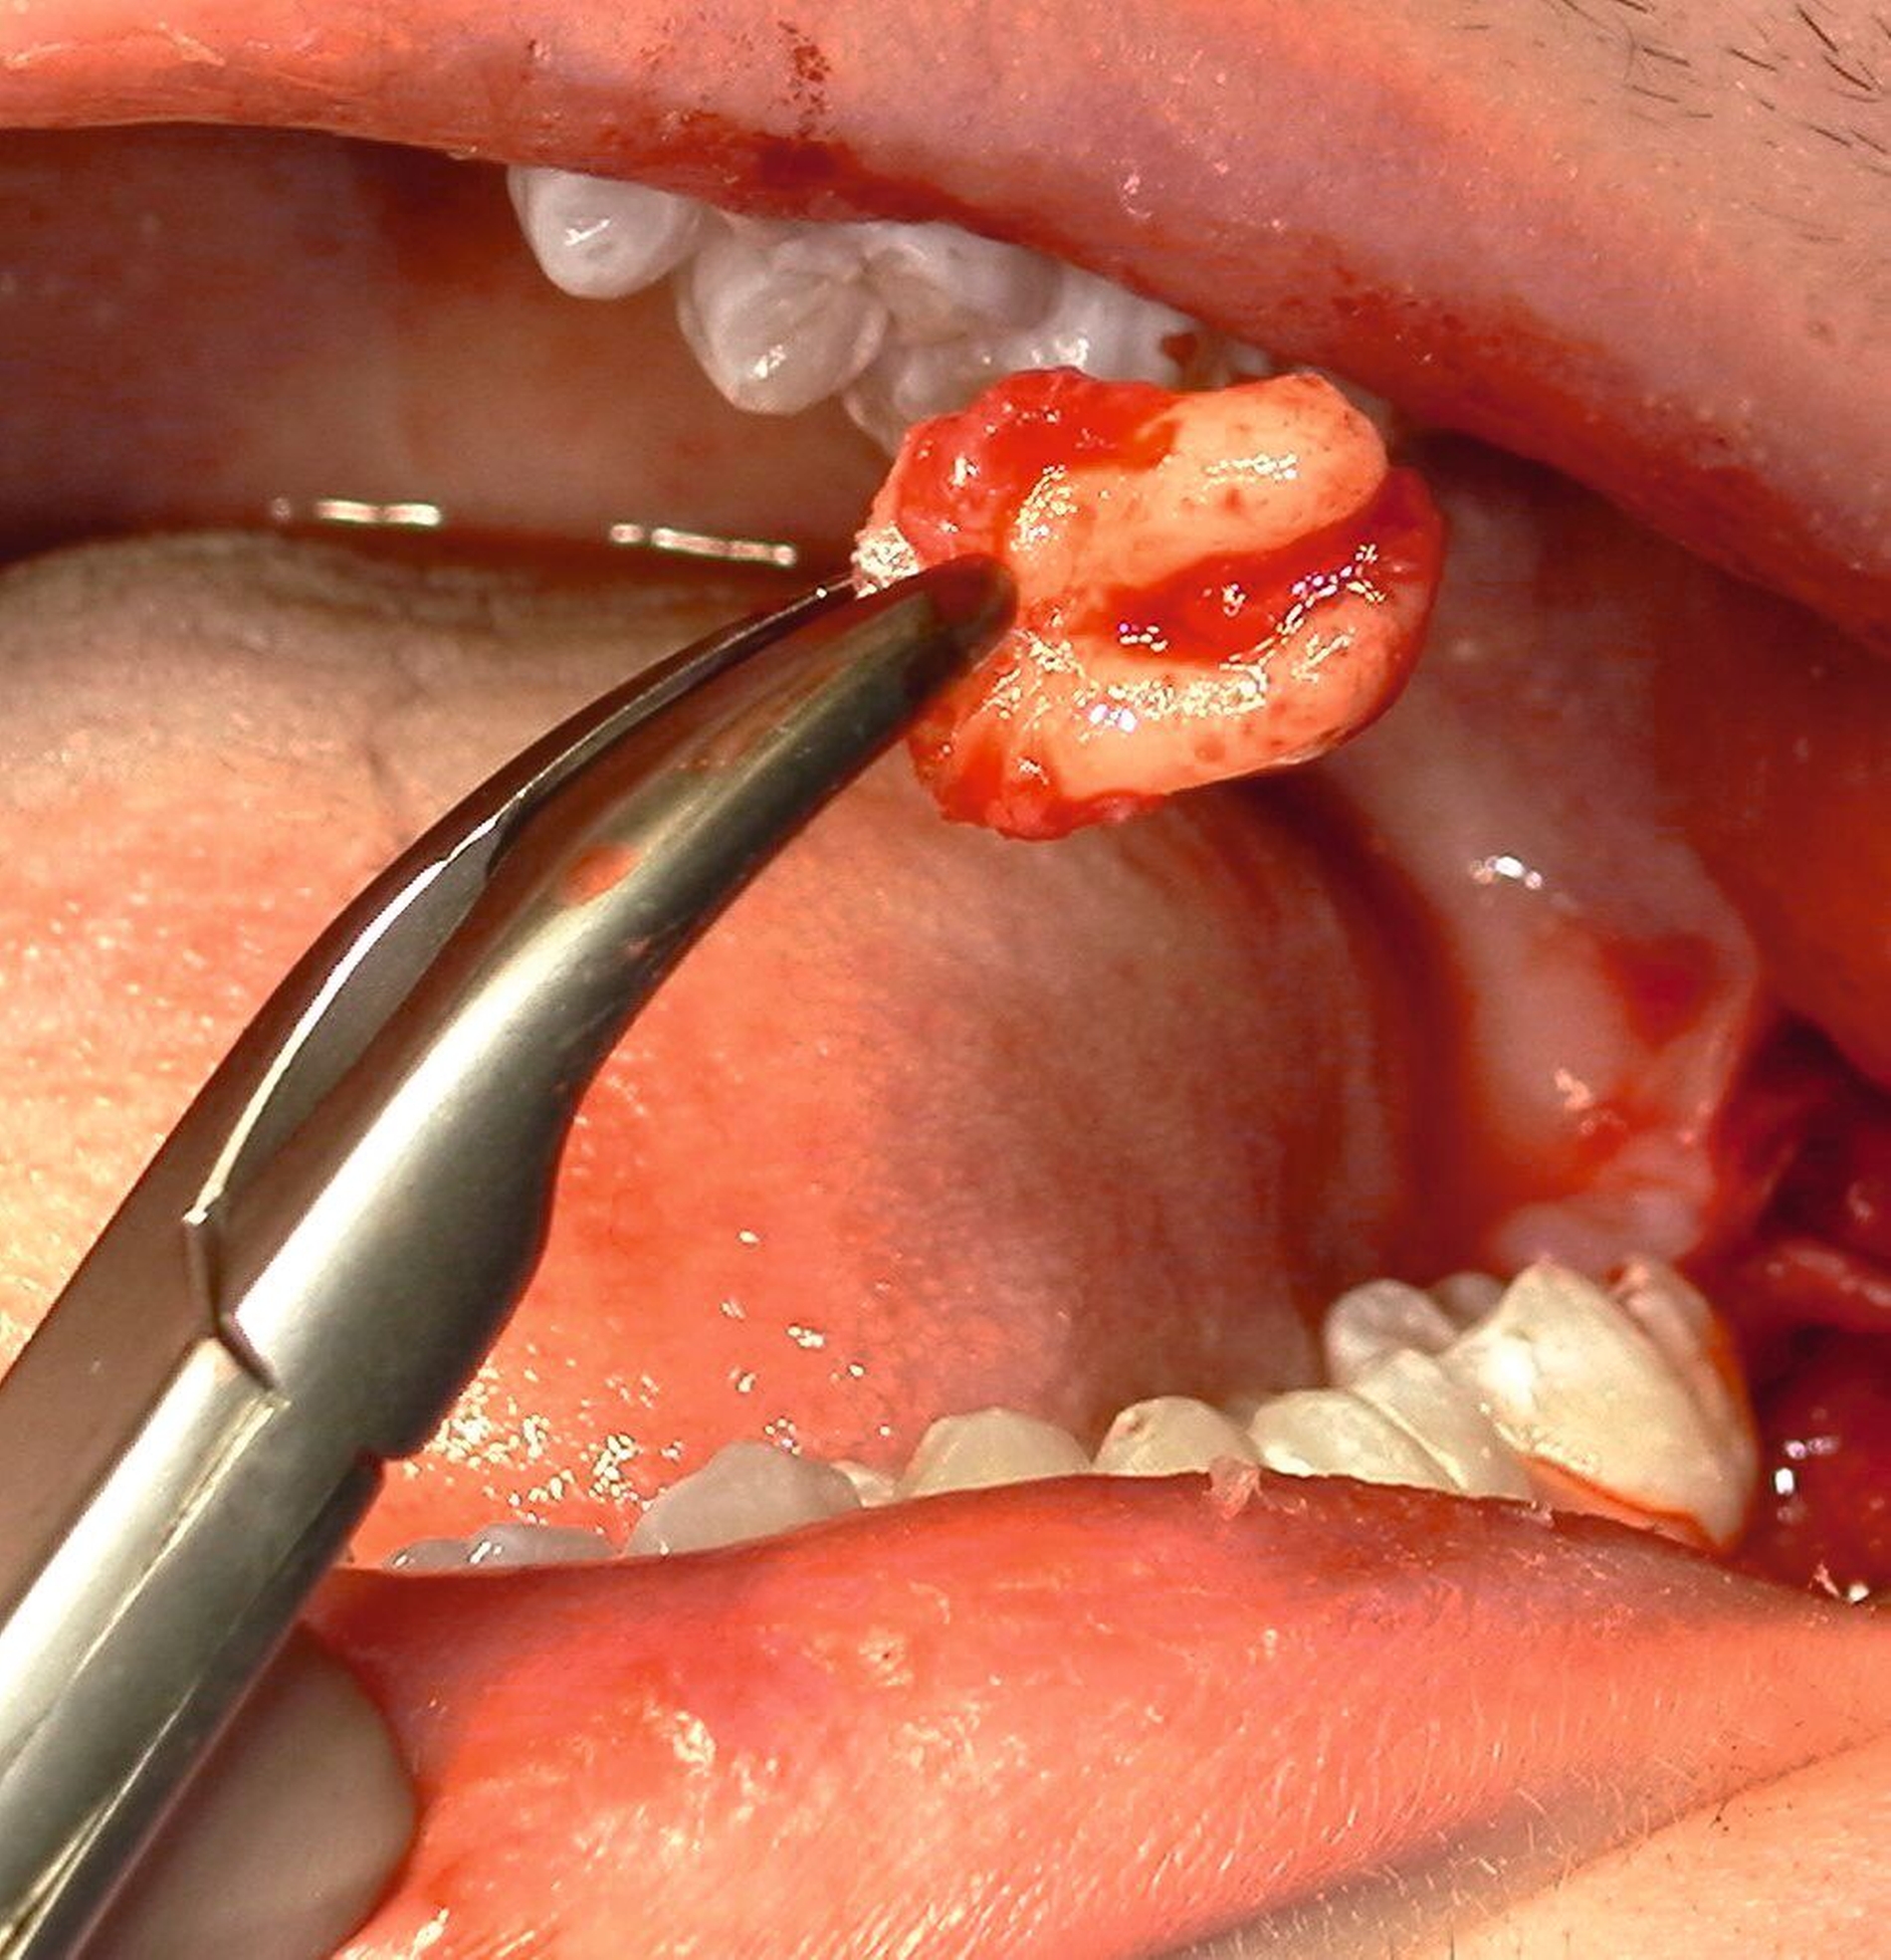

Nach Freilegung des Knochens kann ein Wundhaken nach Langenbeck eingesetzt werden sowie ein Bohr-Raspatorium zum Schutz des N. lingualis subperiostal lingual [Gutwald et al., 2019]. Unter Verwendung eines rotierenden Instruments (Kugel- und Lindemann-Fräse) oder Piezochirurgie wird der Knochen im Bereich der Zahnkrone abgetragen und diese freigelegt (Abbildung 8). Danach kann der Weisheitszahn vorsichtig mithilfe eines Bein‘schen Hebels anluxiert oder, falls dies noch nicht gelingt, mittels einer Lindemann-Fräse geteilt werden. Dabei wird am größten Kronendurchmesser die Krone mit der Fräse abgetrennt und die Wurzel anschließend separat entfernt (Abbildungen 9 und 10) [Gutwald et al., 2019; Schwenzer, 2019].

Anschließend erfolgt die sorgfältige Kürettage unter Schutz des am Boden der Extraktionsalveole liegenden Canalis mandibularis, die Entfernung von Granulationsgewebe sowie des Follikelepithels. Die Wurzelspitze sollte auf Vollständigkeit überprüft werden, um eine Wurzelfraktur auszuschließen (Abbildung 11).